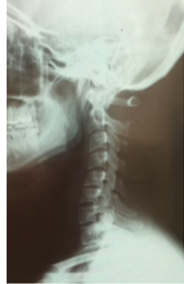

頸椎ヘルニアでお悩みの方 必読です!

病院でレントゲン・CT・MRIを撮って、『頸椎ヘルニアですね。手術orクスリしか方法はない!』と医師から言われることがよくあります。

頸椎ヘルニアの完治は手術してヘルニアをとる事しかありません。

実際に頸椎ヘルニアを完治させるには手術しかありません。